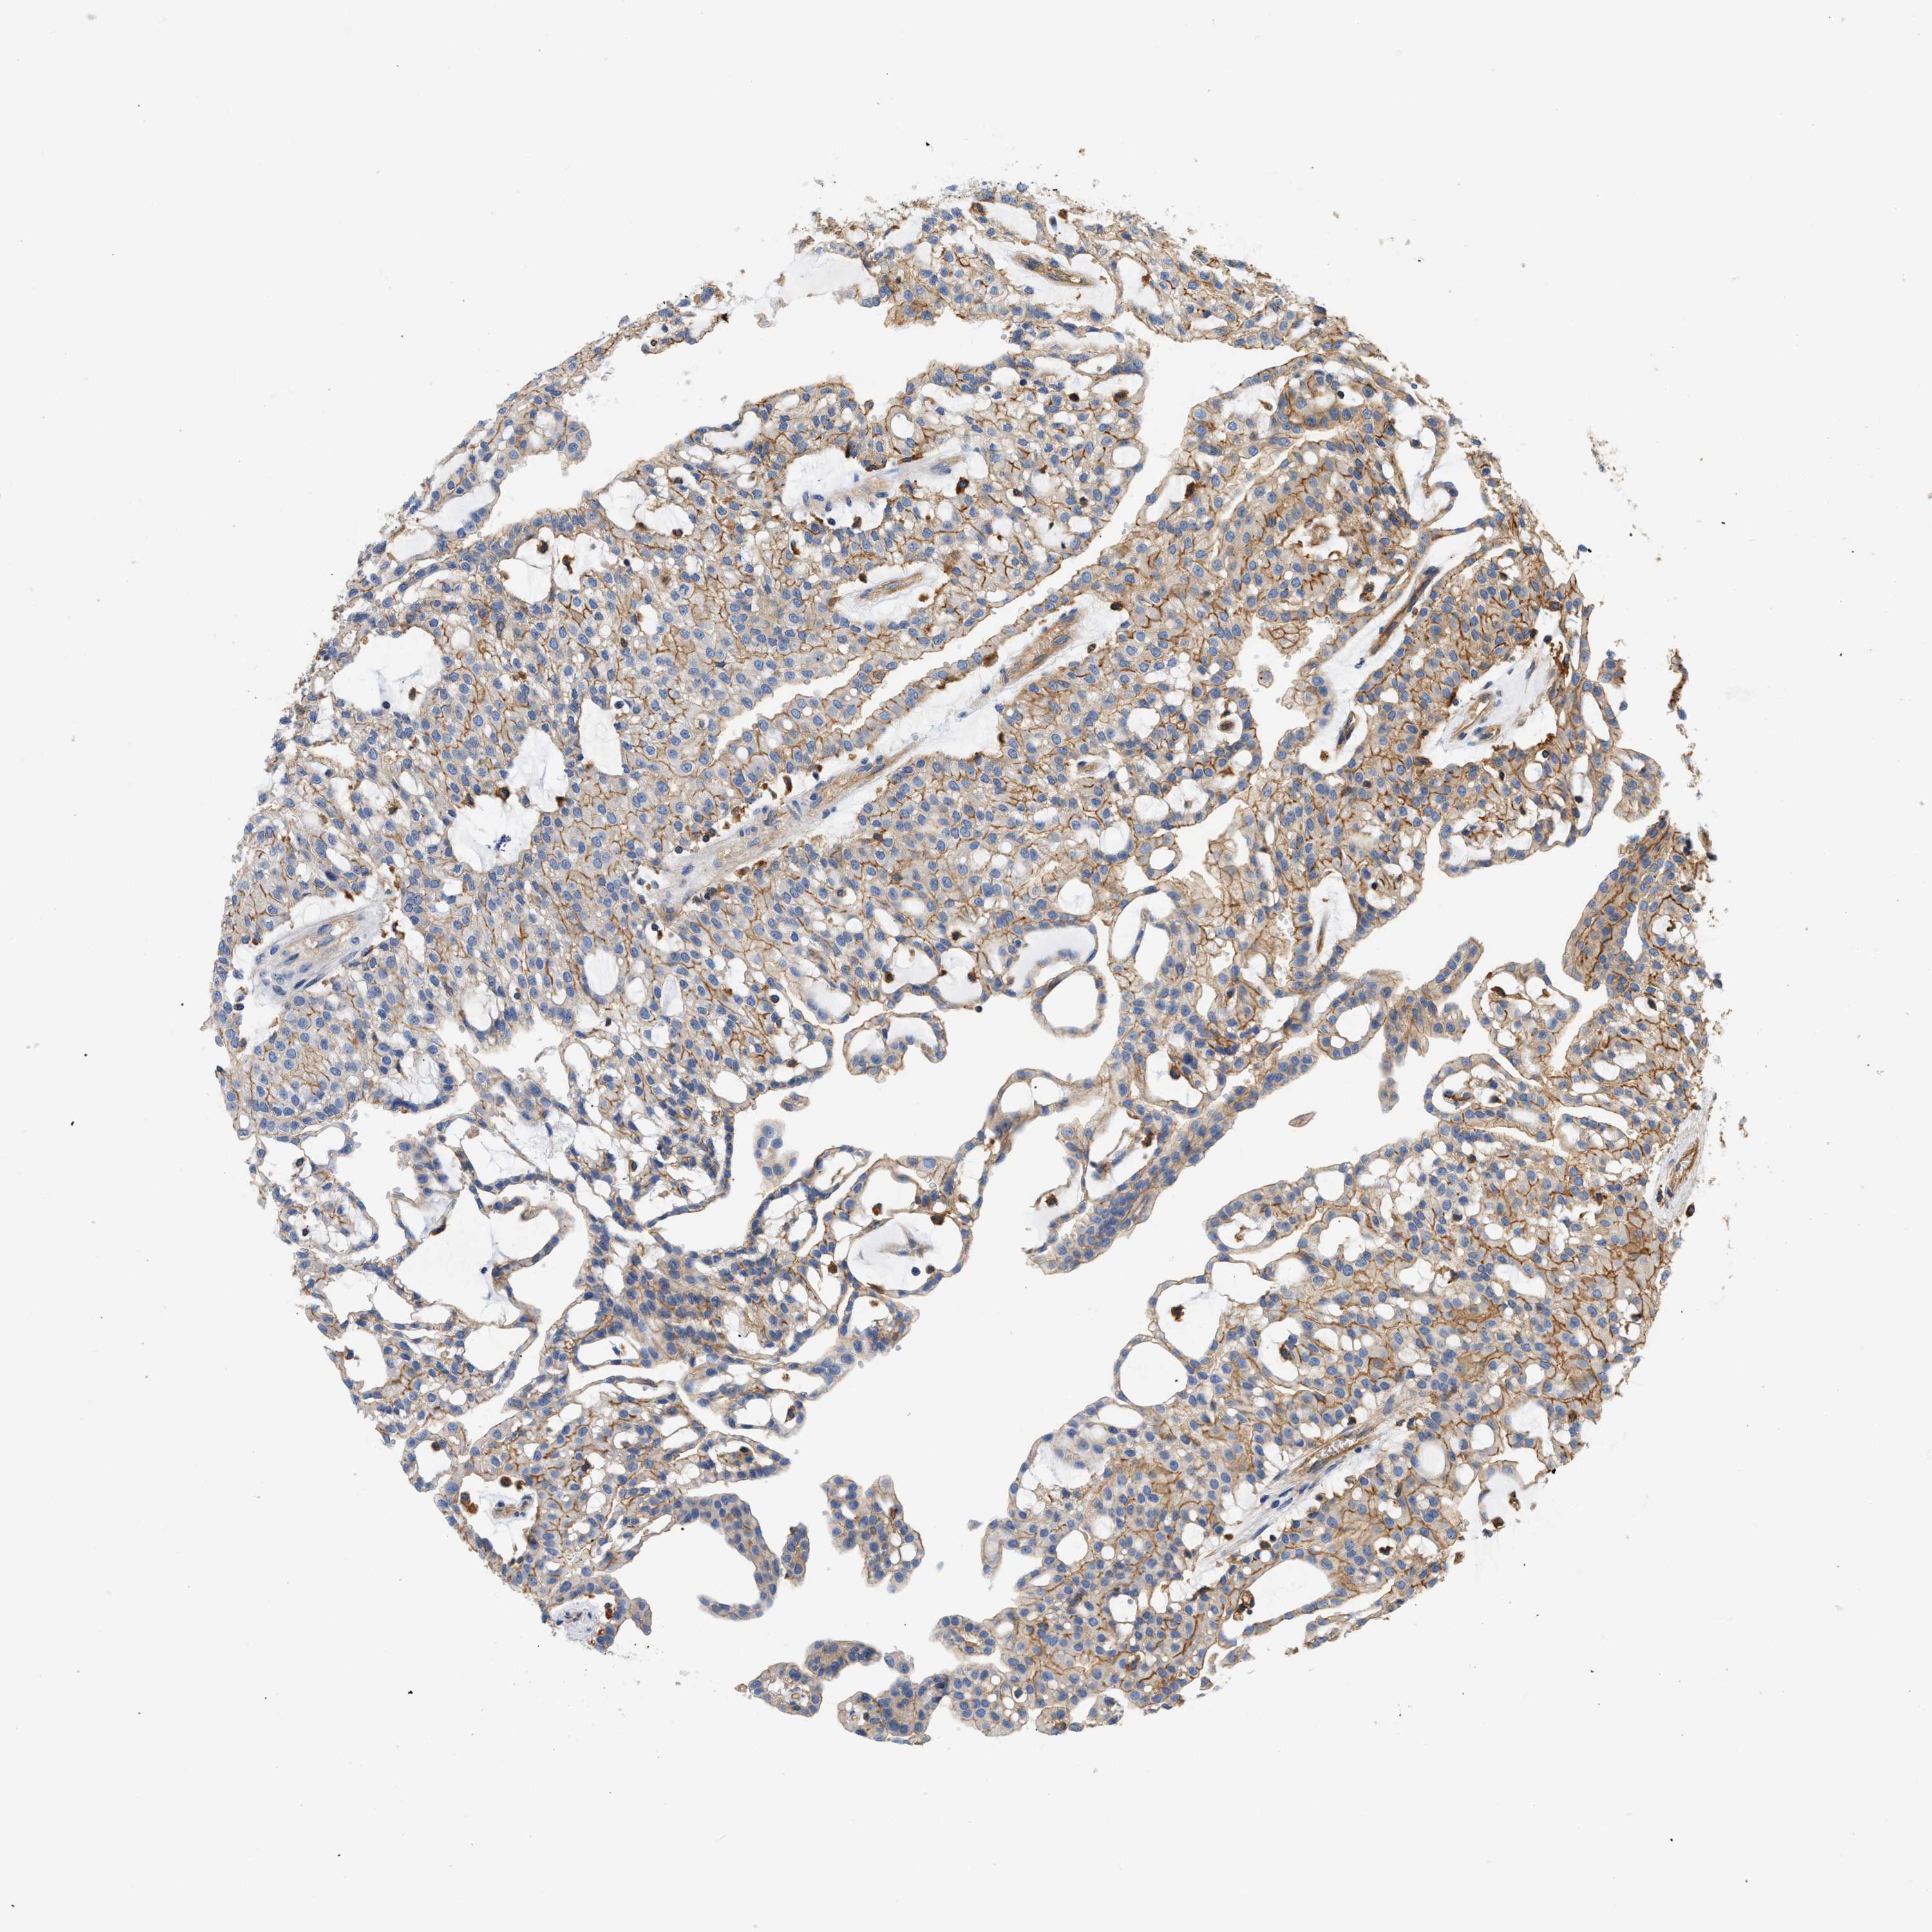

KIDNEY RENAL CLEAR CELL CARCINOMA (TCGA) - Interactive survival scatter ploti

The Survival Scatter plot shows the clinical status (i.e. dead or alive) for all individuals in the patient cohort, based on the same data that underlies the corresponding Kaplan-Meier plots. Patients that are alive at last time for follow-up are shown in blue and patients who have died during the study are shown in red.

The x-axis shows the expression levels (FPKM) of the investigated gene in the tumor tissue at the time of diagnosis. The y-axis shows the follow-up time after diagnosis (years). Both axes are complimented with kernel density curves demonstrating the data density over the axes. The top density plot shows the expression levels (FPKM) distribution among dead (red) and alive patients (blue). The right density plot shows the data density of the survived years of dead patients with high and low expression levels respectively, stratified using the cutoff indicated by the vertical dashed line through the Survival Scatter plot. This cutoff is automatically defined based on the FPKM cutoff that minimizes the p-score. The cutoff can be changed by dragging the vertical line or by entering a cutoff value in the square labeled "Current cut-off".

Under the Survival Scatter plot the p-score landscape (black curve; left axis) is shown together with dead median separation (red curve; right axis). Dead median separation is the difference in median mRNA expression between patients who have died with high and low expression, respectively. It is calculated as follows: median FPKM expression of dead patients with high expression - median FPKM expression of dead patients with low expression. This is intended to aid the user in visually exploring custom cutoffs and the associated p-scores and dead median separation.

Individual patient data is displayed and can be filtered by clicking on one or more of the category buttons on the top of the page. Categories describing expression level and patient information include: high, low, alive, dead, female, male and tumor stages. The scale of the x-axis can be toggled between linear and log-scale by clicking on the "x log" button. Mouse-over function shows TCGA ID, patient information and mRNA expression (FPKM) for each patient.

& Survival analysisi

Kaplan-Meier plots summarize results from analysis of correlation between mRNA expression level and patient survival. Patients were divided based on level of expression into one of the two groups "low" (under cut off) or "high" (over cut off). X-axis shows time for survival (years) and y-axis shows the probability of survival, where 1.0 corresponds to 100 percent.

GNB4 is not prognostic in Kidney Renal Clear Cell Carcinoma (TCGA)

Best expression cut offi

Based on the FPKM value of each gene, patients were classified into two groups and association between prognosis (survival) and gene expression (FPKM) was examined. The best expression cut-off refers the FPKM value that yields maximal difference with regard to survival between the two groups at the lowest log-rank P-value. Best expression cut-off was selected based on survival analysis .

When clicking on this number, the vertical dashed line indicating cut-off, the interactive survival plot, and the Kaplan-Meier curve will be adjusted to show results based on the best expression cut-off.

: 13.69

TCGA RNA samplesi

RNA-seq data is reported as average FPKM (number Fragments Per Kilobase of exon per Million reads), generated by the The Cancer Genome Atlas (TCGA) .

Normal distribution across the dataset is visualized with box plots, shown as median and 25th and 75th percentiles. Points are displayed as outliers if they are above or below 1.5 times the interquartile range. FPKM values of the individual samples are presented next to the box plot.

Average pTPM 14.2

Number of samples 521